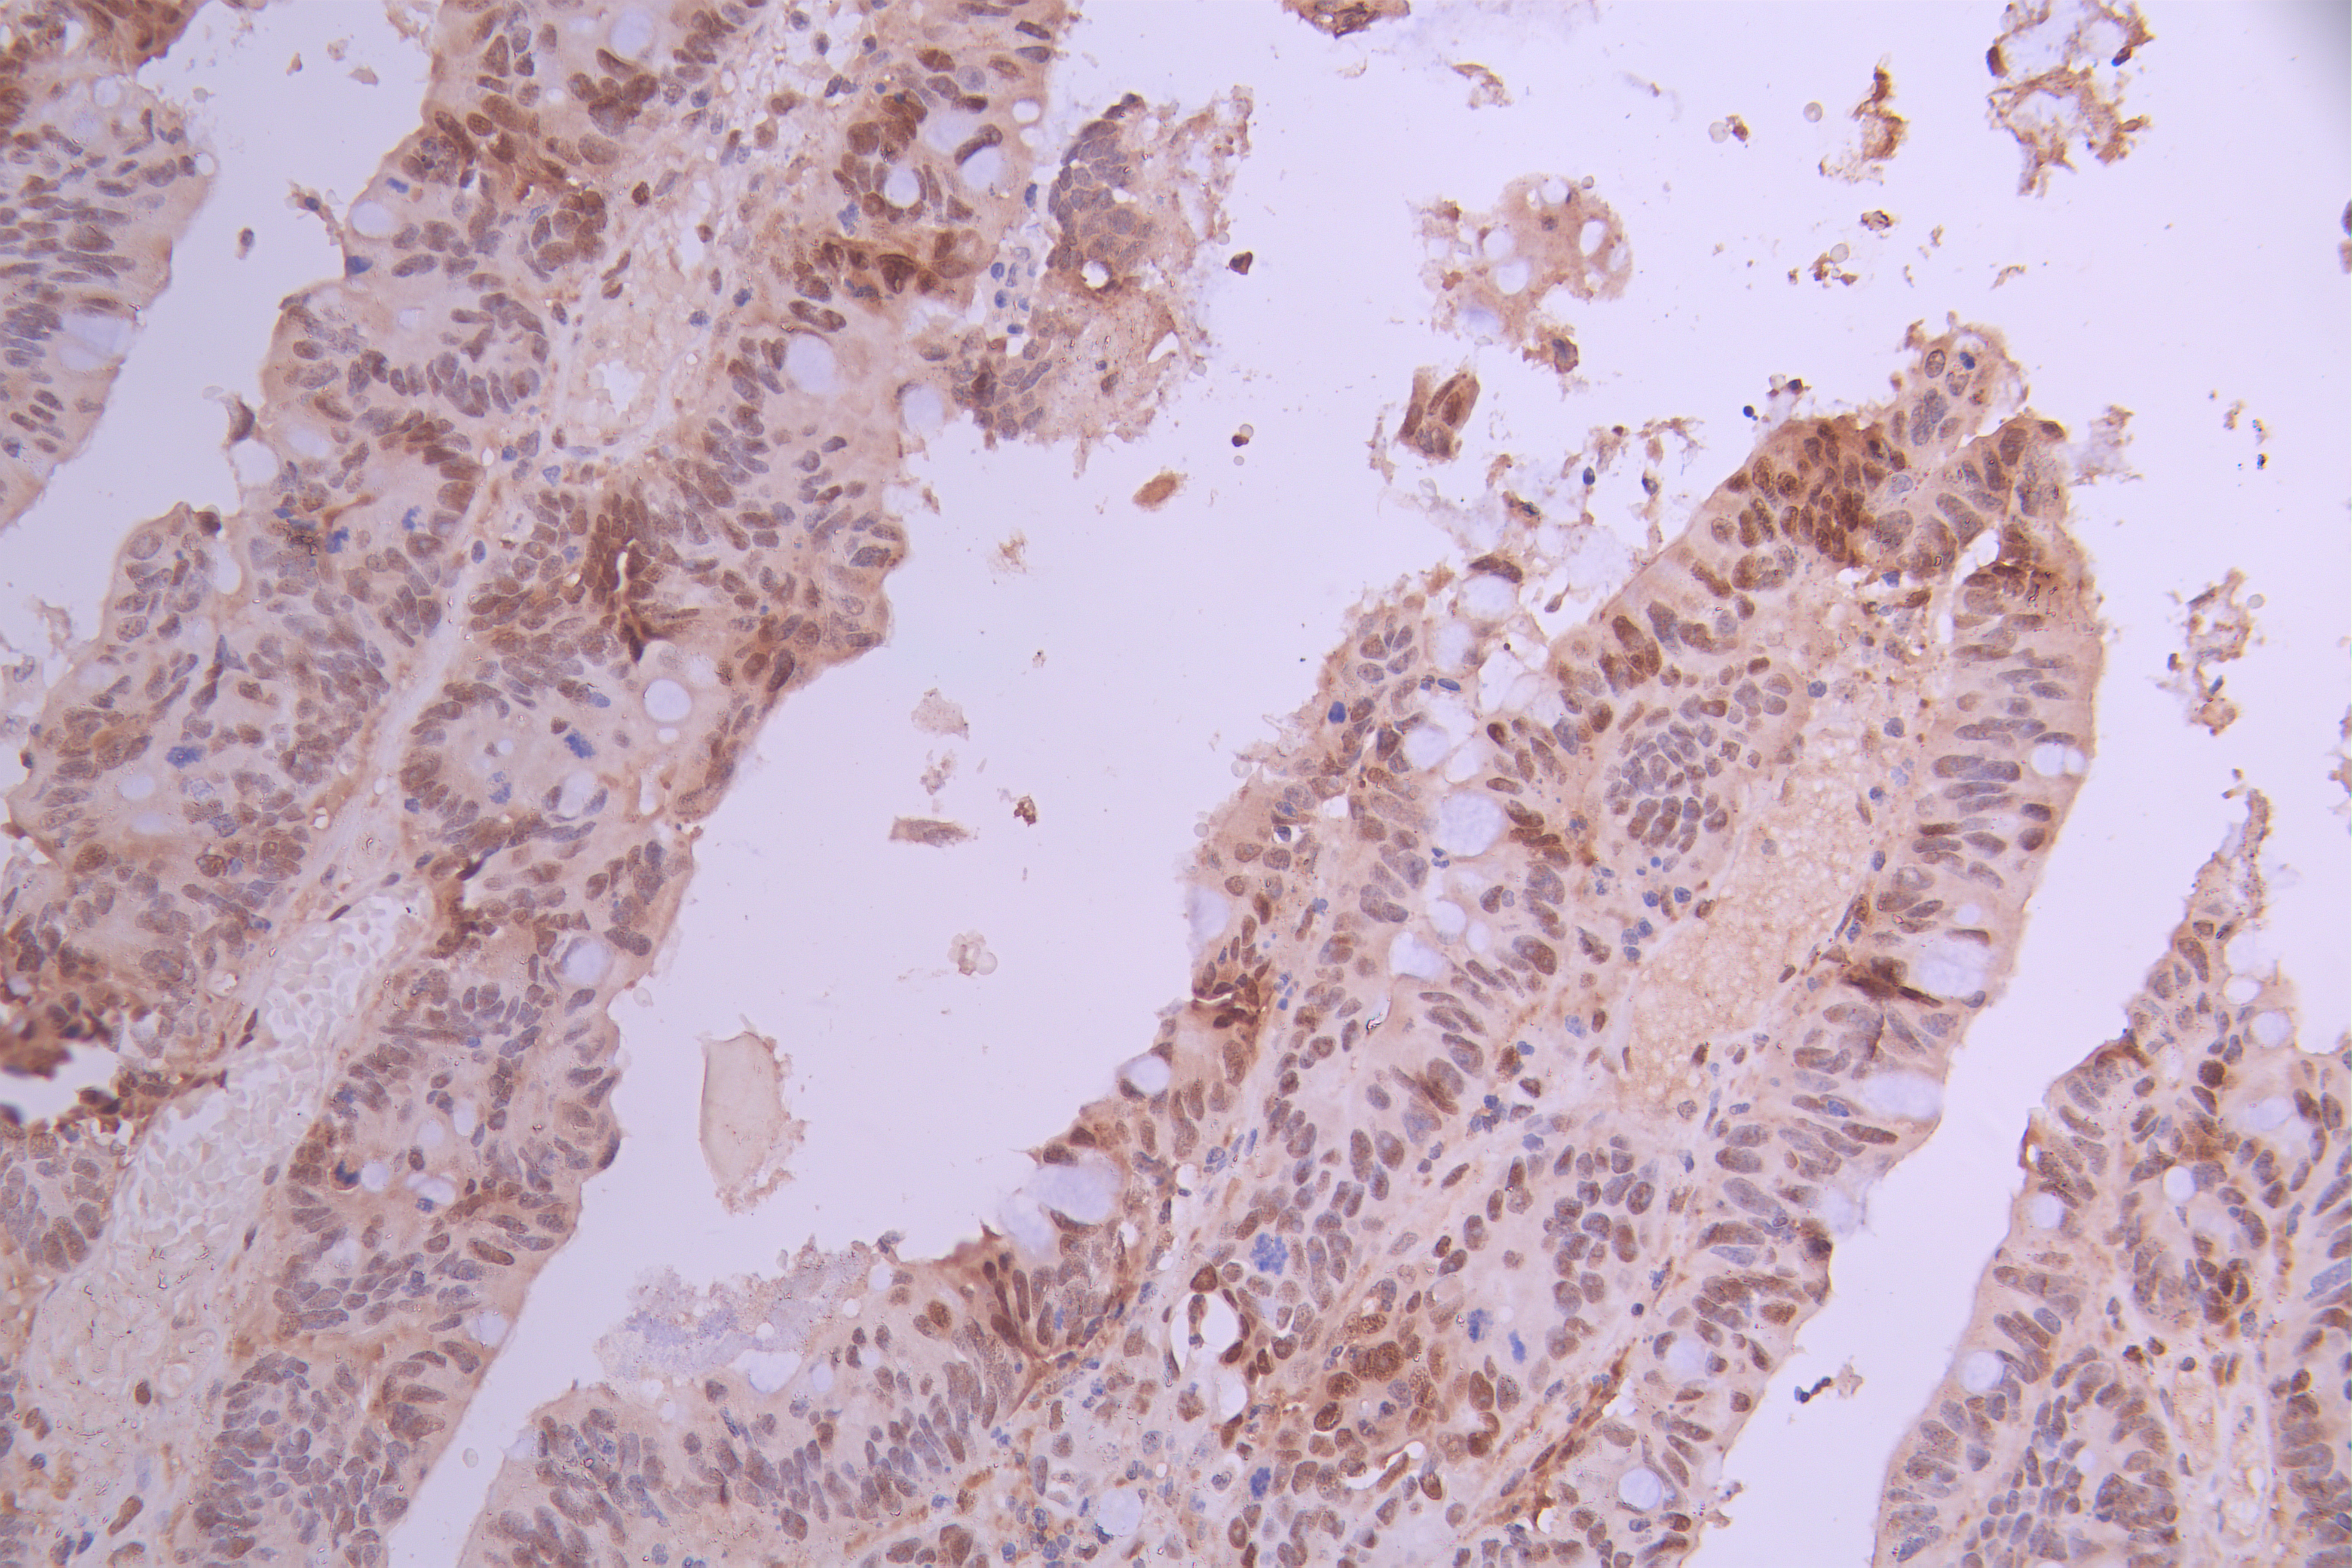

IHC image of CSB-RA276081A0HU diluted at 1:100 and staining in paraffin-embedded human colorectal cancer performed on a Leica BondTM system. After dewaxing and hydration, antigen retrieval was mediated by high pressure in a citrate buffer (pH 6.0). Section was blocked with 10% normal goat serum 30min at RT. Then primary antibody (1% BSA) was incubated at 4°C overnight. The primary is detected by a Goat anti-rabbit polymer IgG labeled by HRP and visualized using 0.05% DAB.

IHC image of CSB-RA276081A0HU diluted at 1:100 and staining in paraffin-embedded human small intestine tissue performed on a Leica BondTM system. After dewaxing and hydration, antigen retrieval was mediated by high pressure in a citrate buffer (pH 6.0). Section was blocked with 10% normal goat serum 30min at RT. Then primary antibody (1% BSA) was incubated at 4°C overnight. The primary is detected by a Goat anti-rabbit polymer IgG labeled by HRP and visualized using 0.05% DAB.